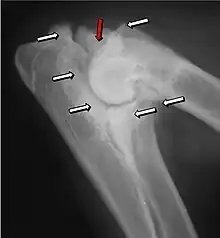

Ununited anconeal process

Most primary lesions are related to osteochondrosis, a disease of the joint cartilage, and osteochondritis dissecans (OCD), the separation of a flap of cartilage on the joint surface. Other common causes of elbow dysplasia include an ununited anconeal process (UAP) and fragmented or ununited medial coronoid process (FCP or FMCP).[1]

In OCD, the normal change of cartilage to bone in the development of the joint fails or is delayed. The cartilage continues to grow and may split or become necrotic. The cause is uncertain, but possibly includes genetics, trauma, and nutrition (including excessive calcium and decreased vitamin C intake).[4] OCD lesions found in the elbow at the medial epicondyle of the humerus are caused by disturbed endochondral fusion of the epiphysis of the medial epicondyle with the distal end of the humerus, which may in turn be caused by avulsion of the epiphysis.[5] Specific conditions related to OCD include fragmentation of the medial coronoid process of the ulna (FMCP) and an ununited anconeal process of the ulna (UAP). All types of OCD of the elbow are most typically found in large breed dogs, with symptoms starting between the ages of 4 and 8 months.[4] Males are affected twice as often as females. The disease often affects both elbows (30 to 70 percent of the time), and symptoms include intermittent lameness, joint swelling, and external rotation and abduction of the paw.[6] Osteoarthritis will develop later in most cases.

UAP is caused by a separation from the ulna of the ossification center of the anconeal process.[7] FMCP is caused by a failure of the coronoid process to unite with the ulna.